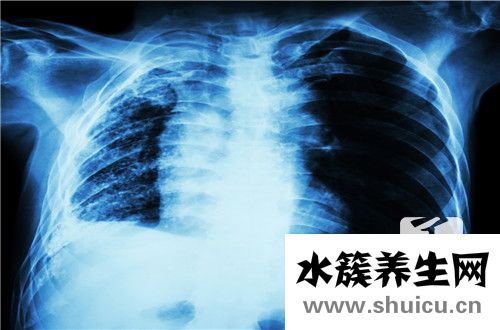

肺鈣化的最常見原因是肺部炎癥。 常見疾病是肺結(jié)核,其次是肺炎。 氣管炎也是由肺癌和其他疾病引起的,尤其是由結(jié)核病引起的肺鈣化。 由于這種疾病會導(dǎo)致感染,因此如果痰中有血液,胸痛和其他癥狀,應(yīng)進(jìn)...